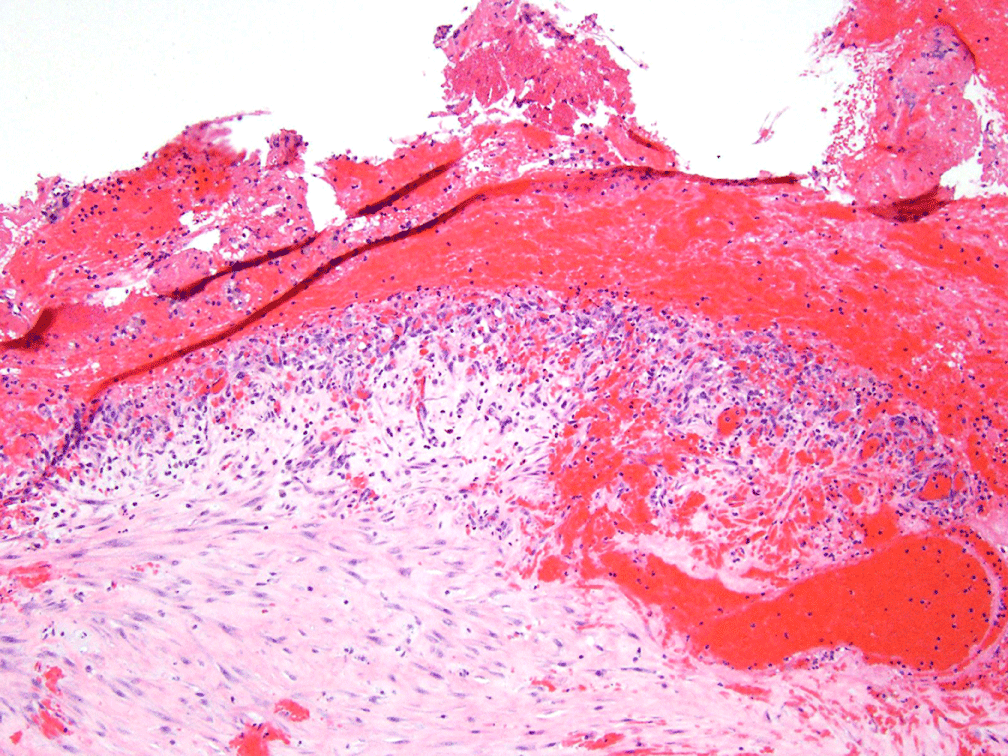

The patient underwent diagnostic laparoscopy with a preoperative differential diagnosis of atypical hemorrhagic cyst versus neoplasm. At surgery a 5 cm × 5 cm × 3 cm chocolate colored cyst was identified on the surface of the bladder serosa consistent in appearance with an endometrioma. The presumed endometrioma was also adherent to the left round ligament and the fundus of the uterus but was not in any way contiguous with the left ovary which was normal. The uterus, fallopian tubes, and right ovary were also normal in appearance, and there was no evidence of peritoneal or other intraabdominal endometriosis. There was no suggestion of a malignancy. During the process of resecting the mass, the cyst ruptured and dark-sanguinous fluid was visualized. The mass was removed, and fluid was evacuated. Pathological evaluation confirmed endometriotic cyst, with evidence of atrophic glands, hemosiderin laden macrophages (pigmented histiocytes) (Figure 3) and endometrial stroma with inflammatory response (Figure 4). The patient's postoperative course was uncomplicated and she was discharged home on the day of surgery on oral contraceptive pills. The patient recovered well and she was without pain on follow up exam.

Figure 4: 4X magnification image showing evidence of blood, stroma, and inflammatory response. View Figure 4